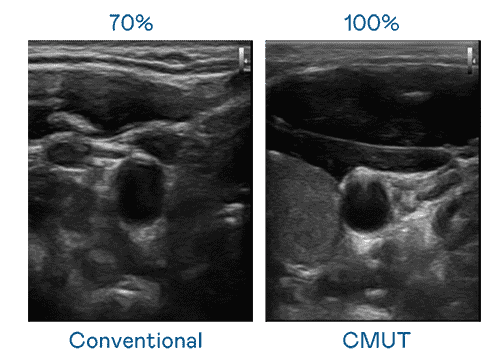

CMUT 技术是一种用电容式微机电元件来产生超音波讯号的技术。。与传统 PZT 压电式技术相比,,,,CMUT 频宽增加 30%,,更宽频的超音波讯号让影像解析度大幅提升,,是实现高影像品质医疗超音波扫描、、促进精准医疗发展的关键技术。。。。

大频宽带来超清晰影像

超音波影像的解析度高低,,,首先取决于探头能发出的讯号频宽。。彩运网 CMUT 可提供高清晰的超音波讯号,,提供高频宽、、高灵敏度、、、、影像纹理细节更高的超音波影像,,,协助医护人员缩短影像判读时间及利用精准的医疗影像进行诊断。。。